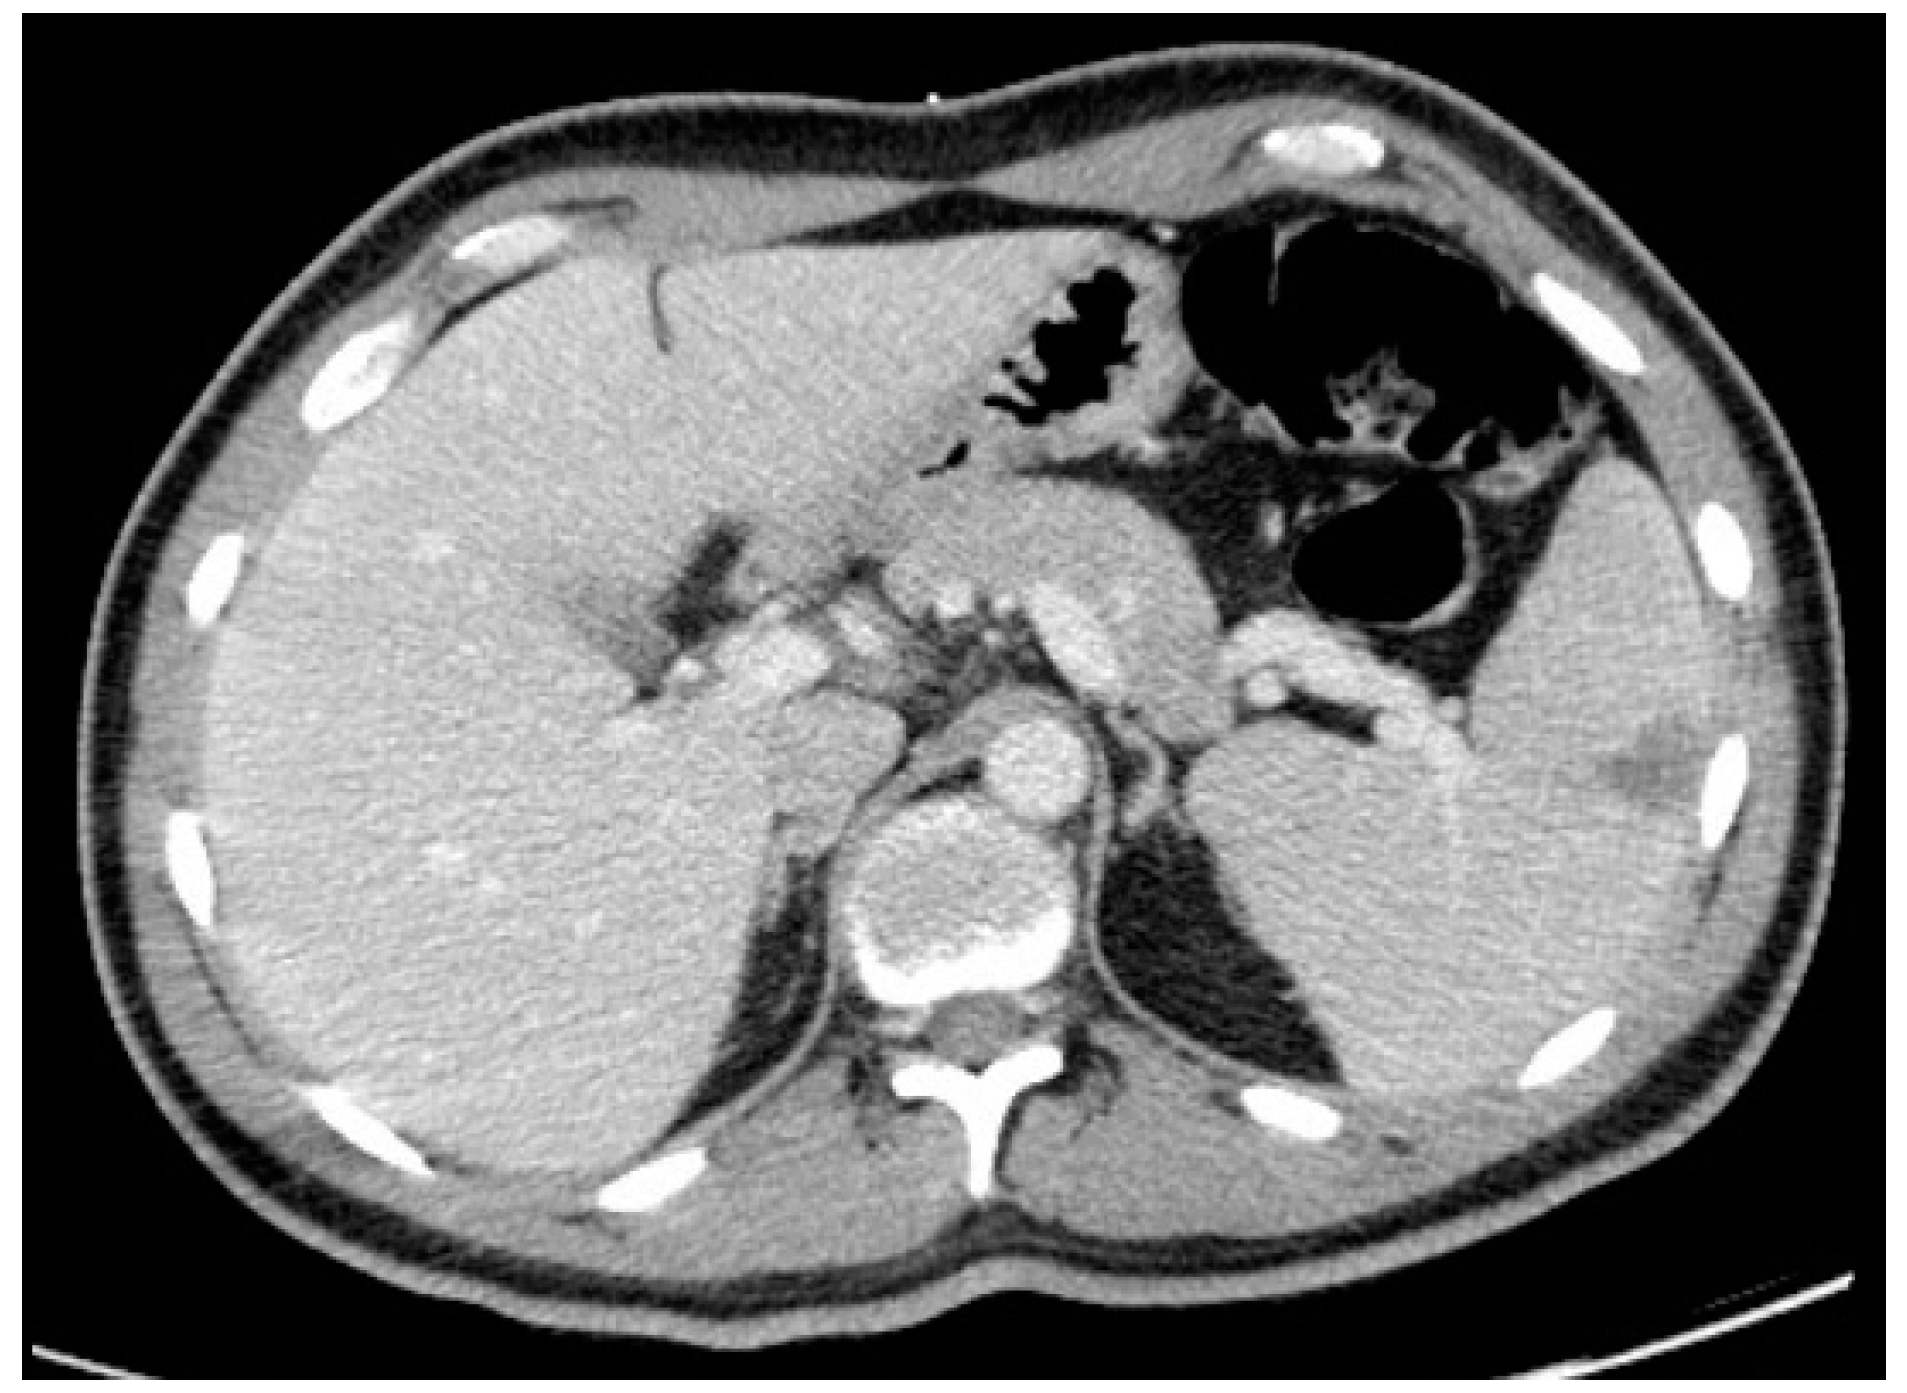

In December 2017, he was admitted to the emergency room with left central facial palsy and dysarthria. Cranioencephalic magnetic resonance showed an ischaemic lacunar lesion in the right corona radiate (Figure 1). Transoesophageal echocardiography (TEE) showed a prolapsed mitral valve, with suspected rupture of the anterior leaflet and severe regurgitation. Holter and ecodoppler of neck vessels were unremarkable. Blood analysis showed microcytic anaemia (haemoglobin 11.3 g/dL), with maintained leukocytosis of 11,000/μL and CRP of 10.2 mg/dL. A small vessel ischaemic disease was diagnosed. He was discharged and sent to cardiology and neurology appointments.

Figure 1. Cranioencephalic magnetic resonance with right ischaemic lacunar lesion in the corona radiata.